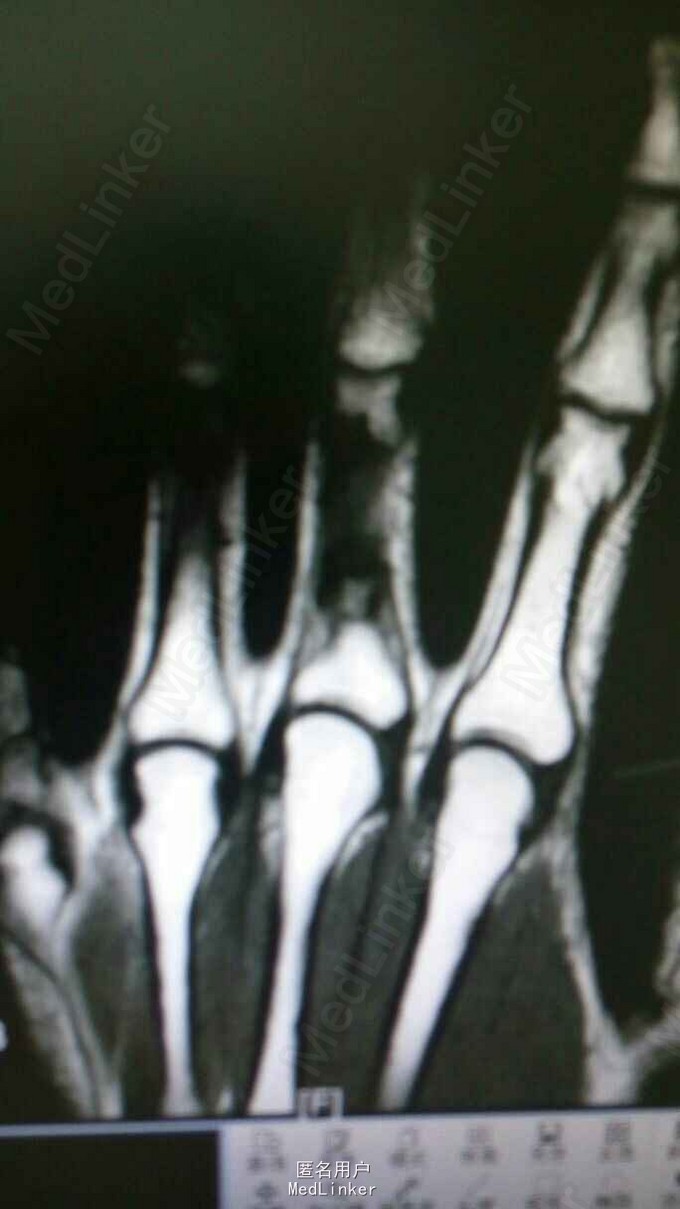

男,30岁。 主诉:发现左中指肿物,伴偶发疼痛2年余。 现病史:患者2年前打篮球致左中指骨折,当地医院检查示左中指近节肿物伴病理性骨折,予保守治疗后骨折愈合,期间患指偶伴疼痛。

查体:左中指压痛(+),未触及骨擦感。 辅查:骨关节螺旋CT平扫:左中指近节指骨骨干见不规则骨质破坏区,关节面完整光滑。MR平扫:考虑为左中指近节内生性软骨瘤伴病理性骨折。

诊断:病理性骨折(左中指近节内生性软骨瘤伴病理性骨折) 治疗:左中指近节肿物开窗刮除+钢板螺钉内固定术。 术后病理提示为内生软骨瘤可能性大。